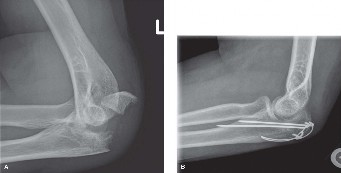

You are consulted to evaluate the right elbow of a 38-year-old female who was involved in a motor vehicle col…